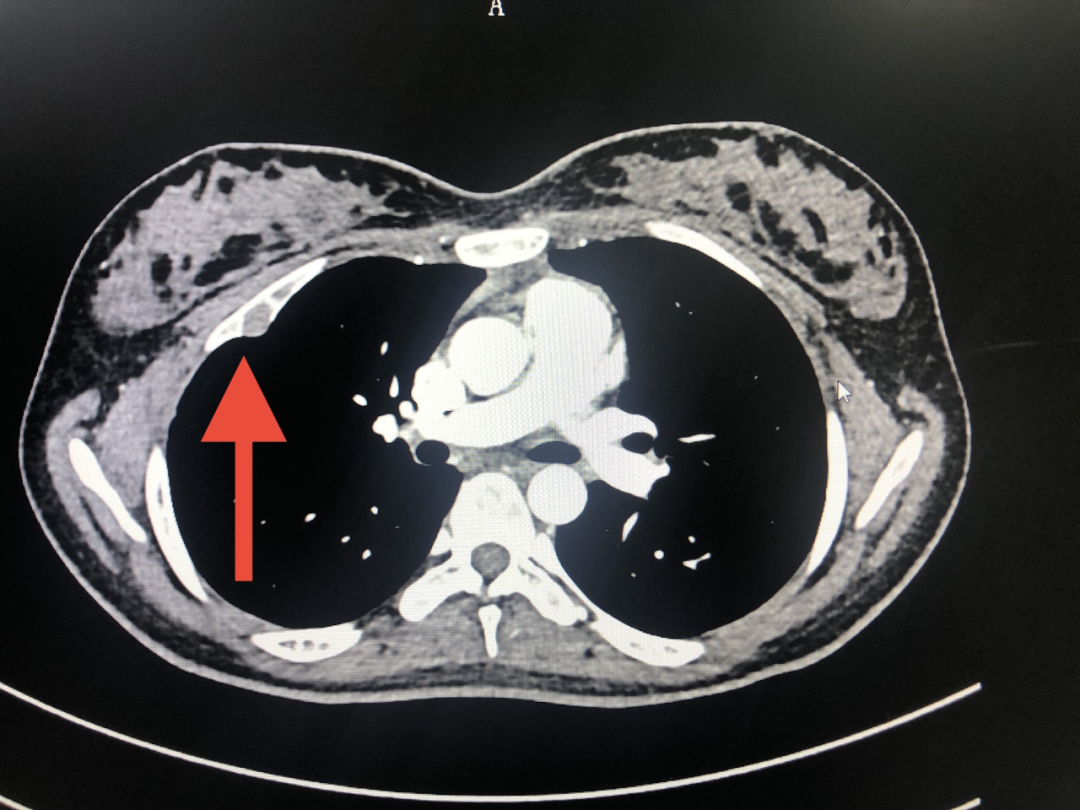

18歲女性患者,因右側(cè)胸壁疼痛就診我院,查胸部CT發(fā)現(xiàn)右側(cè)第3肋骨腫瘤,遂慕名找到了我院院長(zhǎng)、胸心外科主任醫(yī)師許志揚(yáng)及胸心外科副主任許建新主任醫(yī)師團(tuán)隊(duì)。

入院后完善相關(guān)檢查,許建新主任醫(yī)師發(fā)現(xiàn)患者第3肋骨腫瘤正好位于患者乳腺正下方,如果按照傳統(tǒng)的經(jīng)皮手術(shù)路徑,需要將乳腺組織部分掀起才能充分暴露,手術(shù)創(chuàng)傷大,暴露困難且不美觀。考慮到患者年紀(jì)較小以及美觀等因素,許建新主任醫(yī)師、蔡建新主治醫(yī)師決定為患者施行微創(chuàng)全胸腔鏡肋骨腫瘤切除。手術(shù)僅在兩個(gè)2cm小孔以及2個(gè)針眼大小的切口中完成。術(shù)后患者恢復(fù)良好,2天后順利出院。